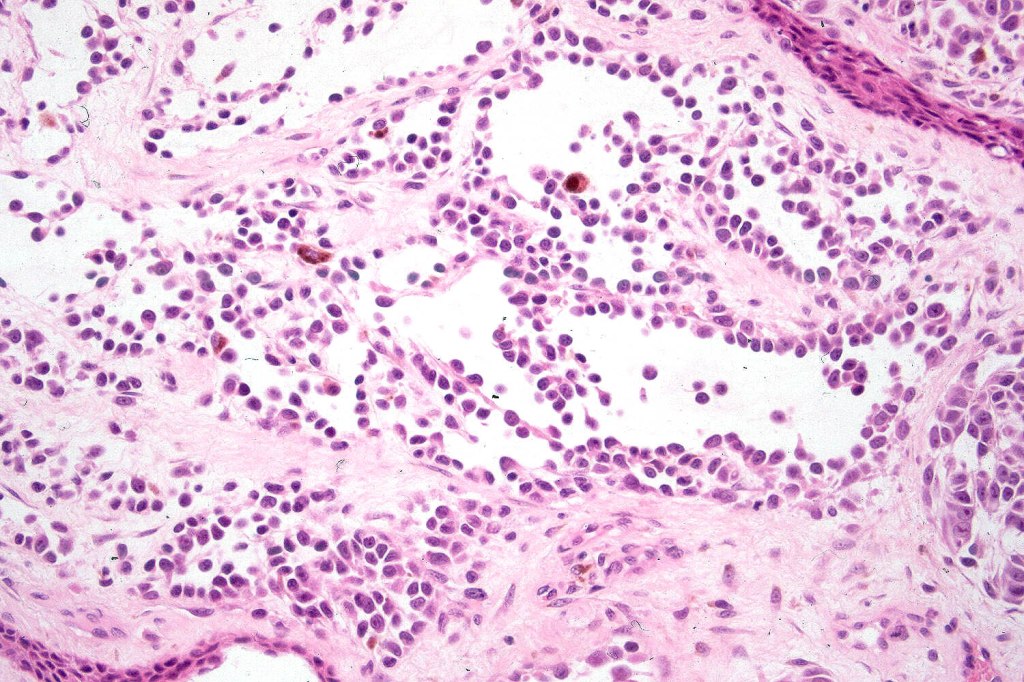

A rare variant of melanoma in which stromal cells produce excess acid mucopolysaccharides inprting a striking myxoid quality. The mucin is Alcian blue & colloidal iron positive, DPAS negative and the melanoma cells stain with typical markeres including S100 & HMB45. It may be seen in primary, recurrent or most often in metastatic lesions. The tumor cells are typically small although occcasionally they are epithelioid. Melanin is often sparse or even avsent making diagnosis difficult. In some examples, a pseudoglandular appearance is seen.

The differential diagnosis is very wide and can include numerous myxoid soft tissue tumors and epthelial mucin-secreting carcinomas. Diagnosis depends on clinical history, mucin stains and the judicious use of immunohistochemistry.